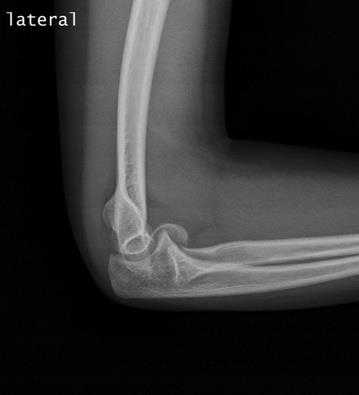

Для определения перелома выполняется рентгенография локтевого сустава в двух проекциях. Этого исследования достаточно в большинстве случаев. Для более детального исследования характера перелома выполняют компьютерную томографию (КТ). С её помощью можно определить насколько разрушен отросток и определиться с тактикой лечения. Выполнять ли операцию и с использованием какой металлоконструкции. Все эти ньюансы очень важны для лучшей фиксации и наилучшего исхода лечения.

Рентгенография

Рентгенография обеспечивает визуализацию плотных анатомических структур, которыми являются ваши кости. Это основной метод диагностики переломов в области локтевого сустава.

Рентгенограмма локтевого сустава в боковой проекции, на которой представлен перелом локтевого отростка со смещением